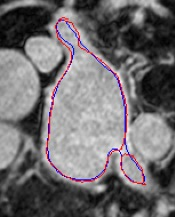

Automated segmentation in medical image analysis is a challenging task that requires a large amount of manually labeled data. However, most existing learning-based approaches usually suffer from limited manually annotated medical data, which poses a major practical problem for accurate and robust medical image segmentation. In addition, most existing semi-supervised approaches are usually not robust compared with the supervised counterparts, and also lack explicit modeling of geometric structure and semantic information, both of which limit the segmentation accuracy. In this work, we present SimCVD, a simple contrastive distillation framework that significantly advances state-of-the-art voxel-wise representation learning. We first describe an unsupervised training strategy, which takes two views of an input volume and predicts their signed distance maps of object boundaries in a contrastive objective, with only two independent dropout as mask. This simple approach works surprisingly well, performing on the same level as previous fully supervised methods with much less labeled data. We hypothesize that dropout can be viewed as a minimal form of data augmentation and makes the network robust to representation collapse. Then, we propose to perform structural distillation by distilling pair-wise similarities. We evaluate SimCVD on two popular datasets: the Left Atrial Segmentation Challenge (LA) and the NIH pancreas CT dataset. The results on the LA dataset demonstrate that, in two types of labeled ratios (i.e., 20% and 10%), SimCVD achieves an average Dice score of 90.85% and 89.03% respectively, a 0.91% and 2.22% improvement compared to previous best results. Our method can be trained in an end-to-end fashion, showing the promise of utilizing SimCVD as a general framework for downstream tasks, such as medical image synthesis and registration.